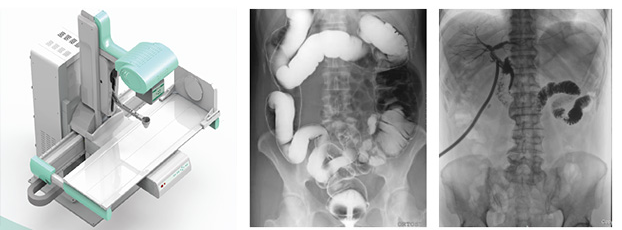

醫(yī)用DR,以其高質量圖像和高工作效率正逐漸替代現(xiàn)在傳統(tǒng)X線攝影技術, 成為當今數(shù)字X線攝影技術的代表,它可以對于人體內部組織進行透視、檢查,從而快速診斷患病情況,及時給予治療。作為一種全新X線成像技術,醫(yī)用DR使整個放射科特別是常規(guī)放射診斷的工作效率和經(jīng)濟效益得到明顯提高。

醫(yī)用DR是臨床應用比較多見的放射科設備之一,其利用X射線對物體的穿透性原理,控制X射線用于對人體組織放射檢查和放射治療。如果您想購買普愛醫(yī)療的醫(yī)用DR,或了解產(chǎn)品具體參數(shù),歡迎聯(lián)系我們。